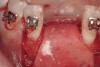

The patient, a 39-year-old woman, presented at the inception of multidisciplinary therapy. Prior to starting comprehensive orthodontic treatment, it was determined that tooth Nos. 24 and 25 were deemed hopeless (Figure 3). Cross-sectional views obtained from cone-beam computer tomography (CBCT) demonstrated deficient labial and lingual cortices at the time of presentation (Figure 4 and Figure 5). Full-thickness flap reflection and delicate extractions were done, utilizing periotomes and forceps and taking precaution to avoid unnecessary trauma and further bone loss; tooth Nos. 24 and 25 were removed (Figure 6). Following thorough debridement with ultrasonic and hand instrumentation, the defects were obturated with a mineralized allograft (freeze-dried bone allograft [FDBA], Musculoskeletal Transplant Foundation [MTF] Tissue Bank, www.mtf.org) (Figure 7). For purposes of graft containment, a traditional barrier membrane may have been chosen; however, due to the compression of the overlying flap and an anticipated 6 to 9 months before implant placement was expected to occur, a thin or knife-edge crest ridge anatomy could result in this area. Therefore, a rigid, resorbable mesh was utilized to provide graft containment and space maintenance (Figure 8). This PLGA-composed mesh was trimmed extraorally to the desired size of the defect, then placed in a sterile, warm water bath at 70°C for about 10 seconds. This temporary warming allows for 3-dimensional (3-D) contouring of the flat mesh to the desired shape needed to reconstruct the alveolar ridge. To prevent movement of the mesh in situ, it was affixed to the labial cortex with screws composed of the same PLGA polymer. A dermal allograft was placed over the graft site to augment the volume of soft tissue in this area of typically thin keratinized mucosa (Figure 9). The flaps were closed in a tension-free manner after a facial periosteal-releasing incision (Figure 10).

Figure 3  Pre-extraction situation. Tooth Nos. 24 and 25 were planned for extraction, and simultaneous ridge augmentation was planned. Implant placement in these two positions at the conclusion of active tooth movement was also planned.

Figure 3

Figure 6  Following extractions, it was possible to visualize the facial and lingual bony walls.

Figure 6